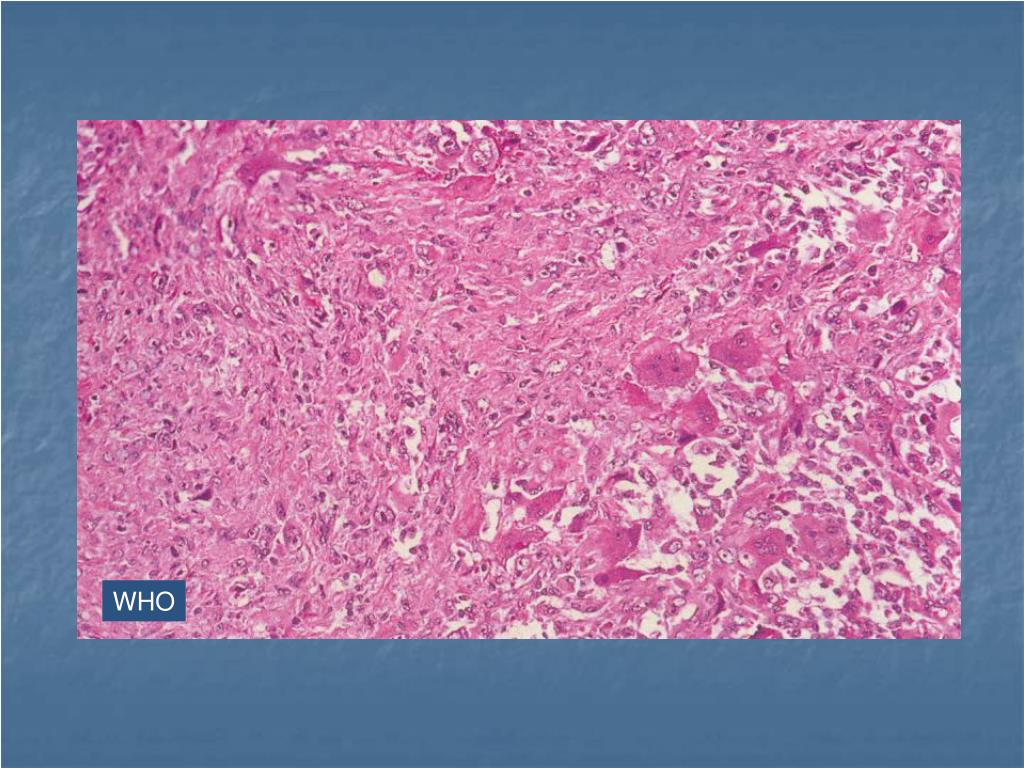

37. WHO

38. WHO